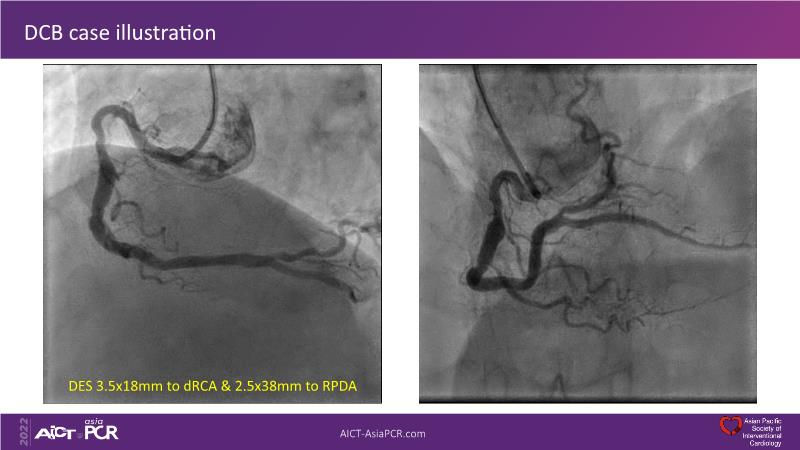

Consult this session to understand the technology and scientific evidence of the novel sirolimus drug-coated balloon, to learn its utility for PCI in a variety of lesion and patient subsets and to understand the evidence and outcomes in real-world patients.

- To learn the utility of the DCB for PCI in a variety of lesion and patient subsets

- To understand the evidence and outcomes of this DCB in real world patients